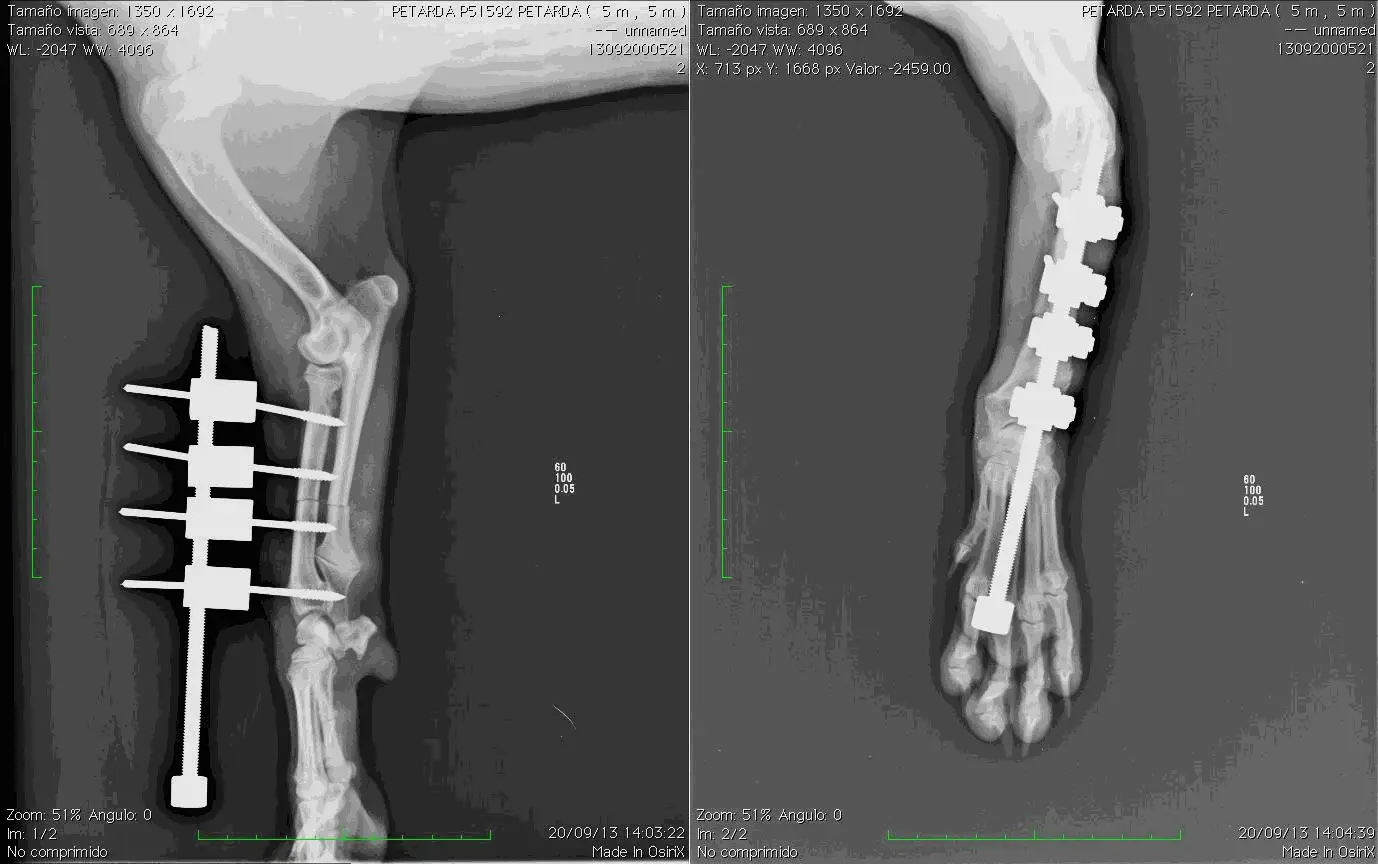

Caso 1

Petarda, beagle, hembra, 5 meses.

Cierre prematuro epífisis distal del radio. Incongruencia codo. Poca desviación de la extremidad

Diferencia de longitud entre ambas extremidades anteriores: 15 mm

Deben realizarse radiografías semanalmente para comprobar que la distracción es efectiva

16-11-13 Cuando ambas extremidades tienen la misma longitud finalizamos la distracción aunque podemos continuar unos mm mas ya que la extremidad no afectada continuará su crecimiento. Muchos perros de unos 15 kg toleran discrepancia de 2 cm o más entre ambas extremidades sin sintomatología